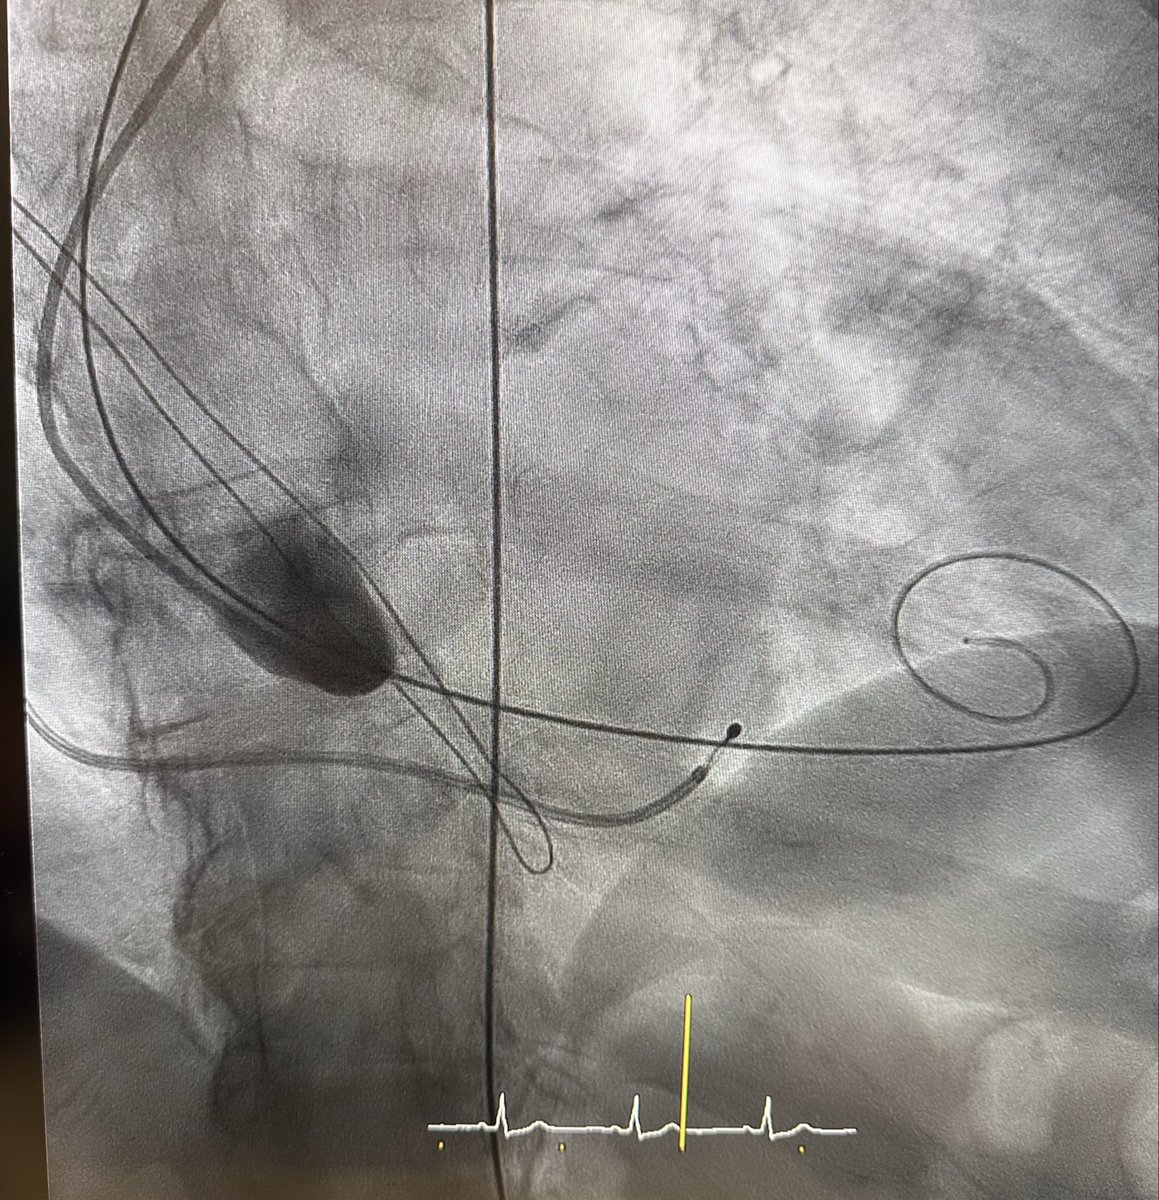

TAV in SAV (Myval 24.5mm in Trifecta 25mm degenerated). Transseptal approach due to difficulties crossing from the aorta to the LV. Excellent final result by echo and angio with a mean gradient of 6 mmHg (Savvywire) @CARDIVAGROUP @MerilLife @pepp183 @Pepa_Palomo @Albabfc